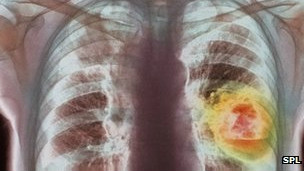

El trastorno, cuyo nombre es bronquiolitis obliterante, es una afección pulmonar obstructiva que dificulta el flujo del aire a los pulmones y es irreversible.

La enfermedad bloquea el movimiento del aire en los pulmones.

"En esta enfermedad, las vías aéreas más pequeñas en los pulmones, los bronquiolos, desarrollan cicatrices y se ven constreñidos, bloqueando el movimiento del aire", informan los CDC.